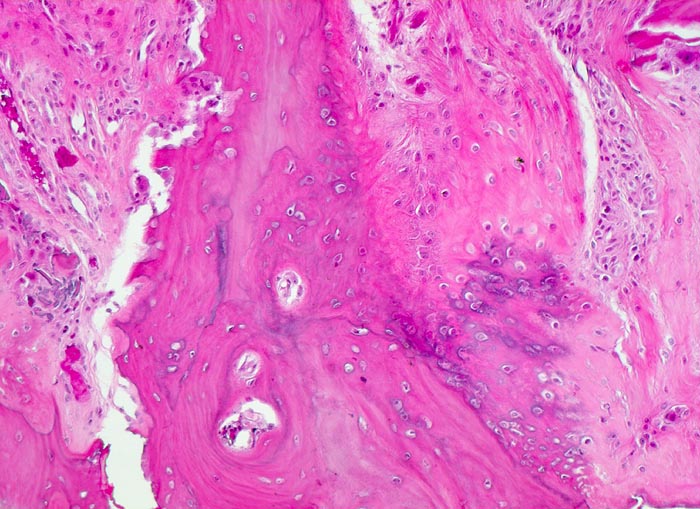

aseptische Femurkopfnekrose

Knochen, Femurkopf

Gesteigerte Umbauphänomene in der Nekrosezone: Ortsständiger Lamellenknochen wird als Leitschiene zur Fasernknochenneubildung benutzt. Auf der gegenüberliegenden Seite wird der Lamellenknochen von Osteoklasten resorbiert. Kleine avitale Knochensequester. Granulationsgewebe.

Der Patient ist Gastwirt von Beruf und klagt über rasch zunehmende Schmerzen im rechten Hüftgelenk, die auch nachts auftreten. Aufgrund der invalidisierenden Schmerzen wird eine Endoprothese eingesetzt.

Histologie

100